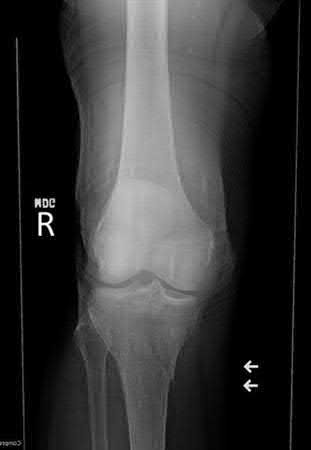

A 27-year-old male is involved in a motor vehicle collision and presents to the ER with the right lower extremity injury shown in Figures A and B. He undergoes immediate closed reduction and the post-reduction CT is shown in Figures C and D. The patient undergoes percutaneous surgical screw fixation of the injury. At 2 years followup, he presents with a supination deformity with decreased eversion of the foot at rest. Radiographs reveal no evidence of talus subchondral sclerosis or collapse. Which of the following is the most likely cause of the finding in this patient?

The patient has sustained a displaced talar neck fracture with medial comminution which requires open reduction and internal fixation to restore anatomic alignment. The patient has likely sustained varus malunion which is a common deformity noted with non-anatomical reduction leading to hindfoot supination and decreased eversion.

Talar neck fractures, while uncommon, can lead to significant morbidity in the ambulatory patient. Treatment of these injuries requires prompt reduction due to the tenuous blood supply to the talus. The most common complications noted after a talar neck fracture are avascular necrosis, subtalar arthritis, tibiotalar arthritis, and varus malunion. A talus varus malunion generally occurs due to medial talar neck comminution and/or non-anatomic reduction of the injury. This deformity can lead to decreased eversion and a supination deformity causing patients to ambulate on the lateral aspect of the foot. These malunions are generally treated with a medial opening wedge osteotomy.

Figures A and B are the Lateral and AP radiographs of a displaced talar neck fracture with tibiotalar dislocation. Figures C and D are the post-reduction sagittal foot CT cuts that reveal a displaced talar neck fracture with medial

comminution.